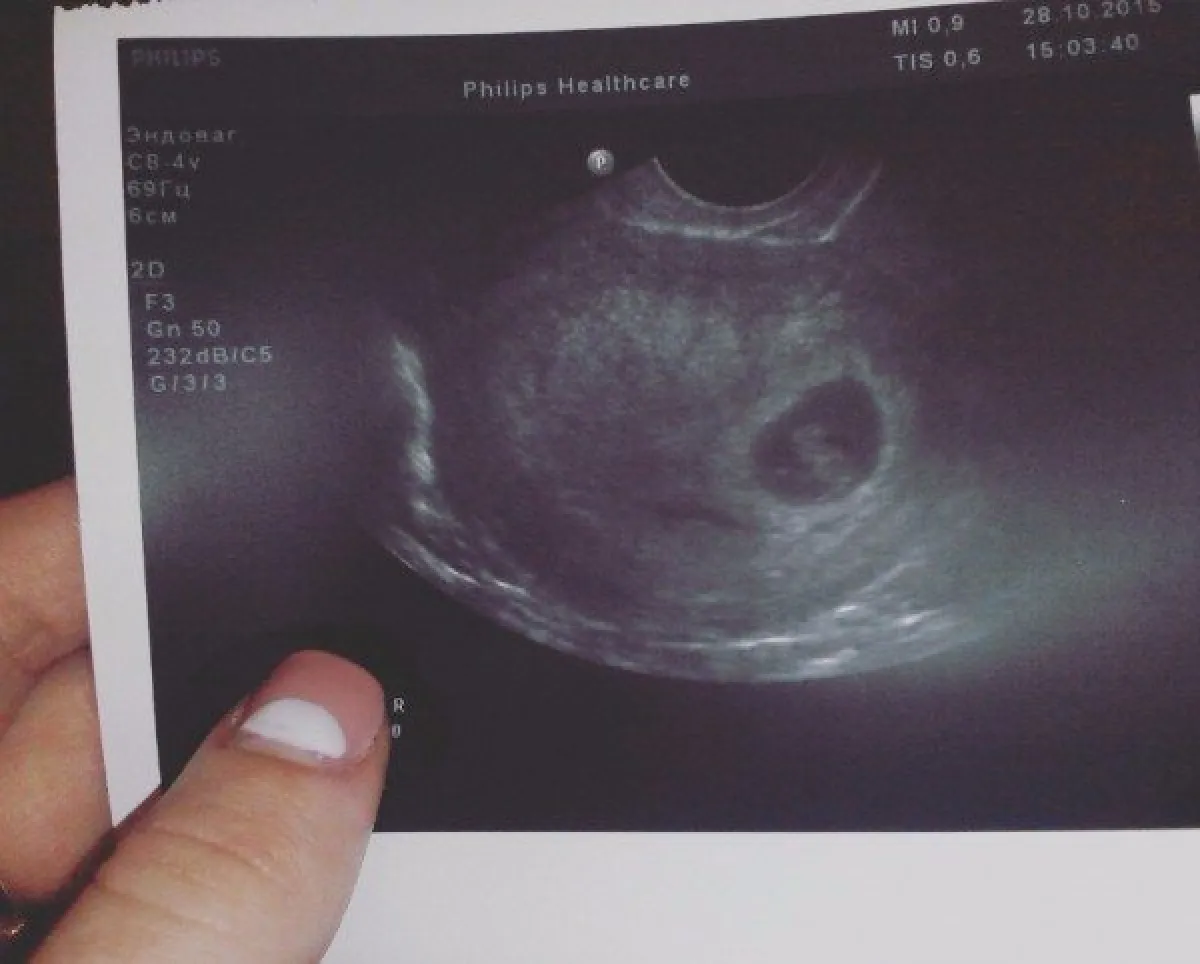

- تحملين بداخلك بداية من هذا الشهر...طفلاً صغيراً؛ برأس كبير وذراعين وساقين، ومعظم أعضائه الداخلية، ولم يعد «مضغة» بل أصبح «جنيناً، يتميز بنمو سريع في جسمه.

- الشهر الثالث مرحلة رائعة ستتخلصين فيه من كل التوعكات وستشعرين بتحسن تدريجي جسدياً ونفسياً، لن تشعري بحركة الجنين...لكنك تعلمين أنه موجود في أحشائك وسوف تنتظرين قدومه بمزيد من الراحة.

- أول تغيير في جسم الحامل يتضح في الرحم الذي يبلغ حجمه في هذا الوقت حبة جريب فروت كبيرة، وقلبك ينبض بوتيرة أسرع من السابق، وقد تشعرين ببعض اللهاث عند قيامك بمجهود جسدي.